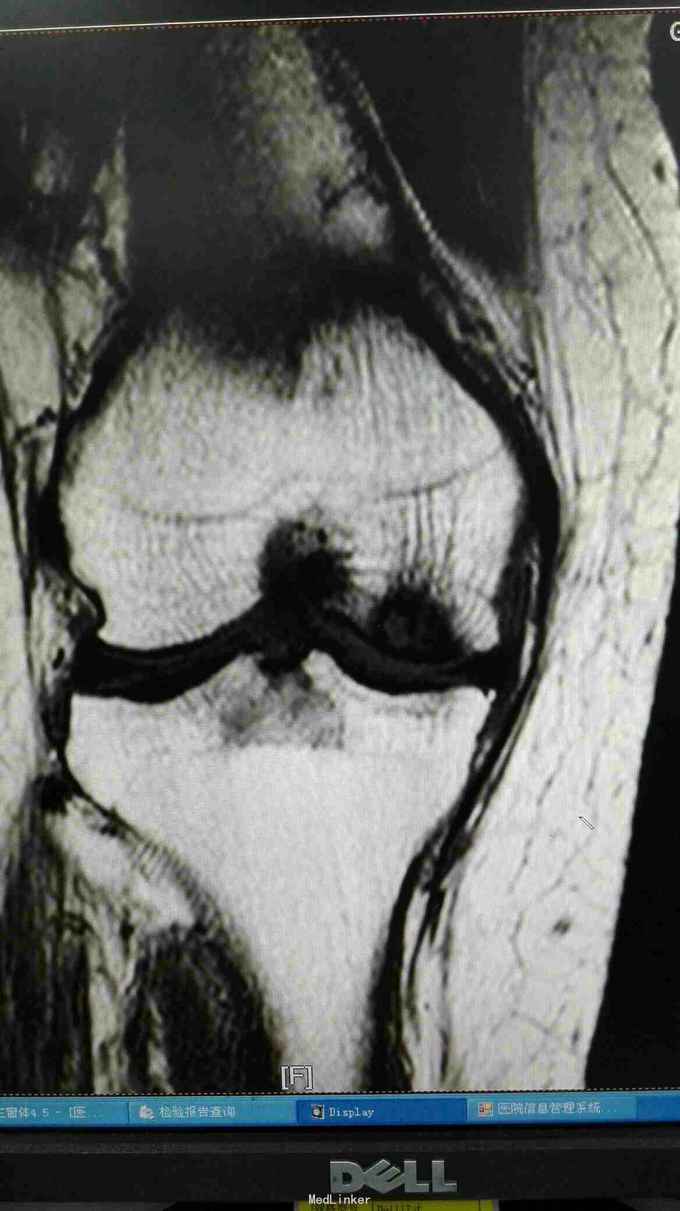

右膝外形正常,皮温正常,右膝内前方压痛(+),前后抽屉试验(-),侧方应力试验(-)、研磨试验内侧(+),关节活动度正常,左膝正常。 站立位膝关节正侧位片提示:右膝关节轻度退行性变,内侧关节间隙稍变窄 右膝关节MRI提示:右股骨内侧髁水肿,考虑局部骨坏死 实验室检查:各炎症指标均正常

诊断:1、右股骨内侧髁骨坏死 2、右膝关节骨性关节炎 治疗:行右膝关节单髁置换术